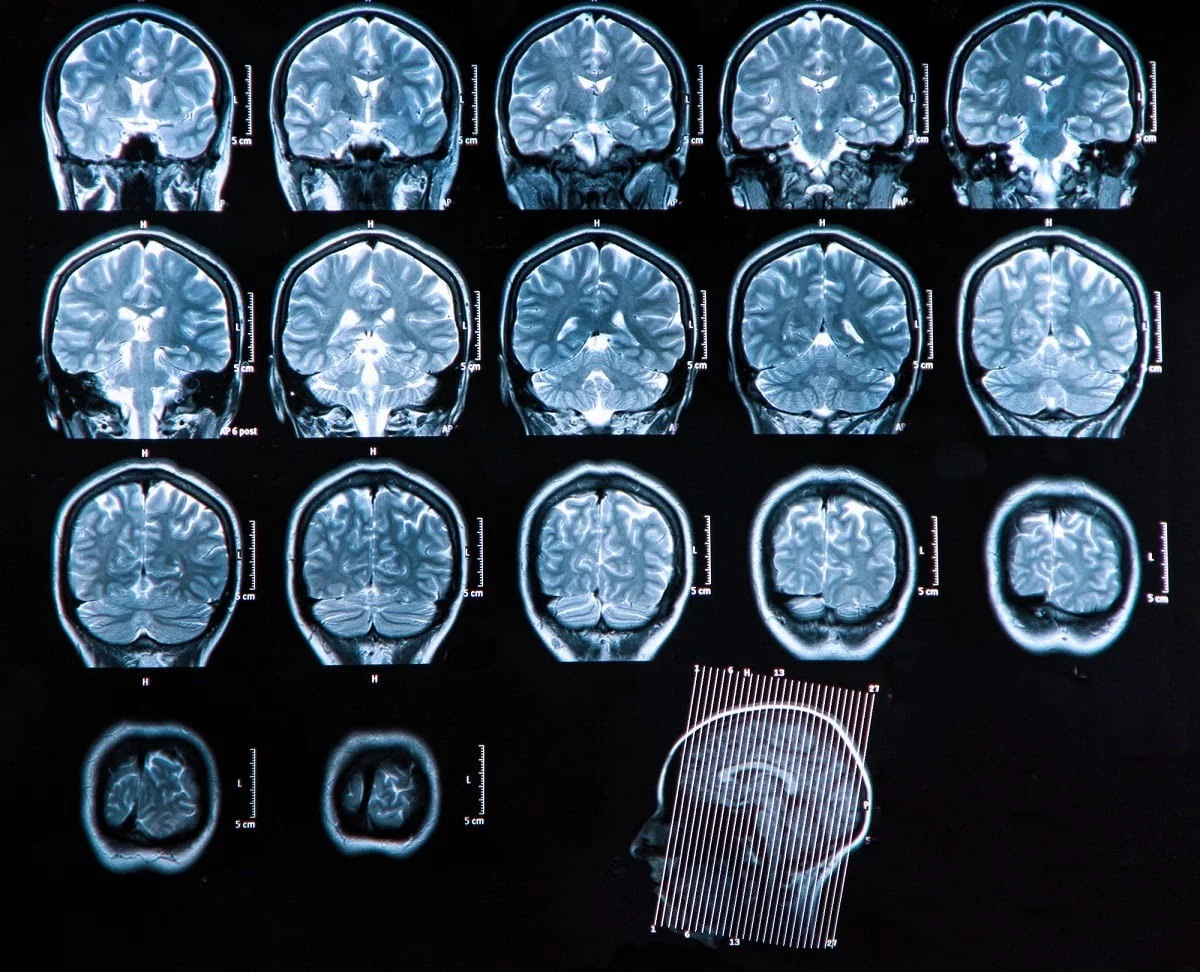

МРТ - сканирование человеческого мозга